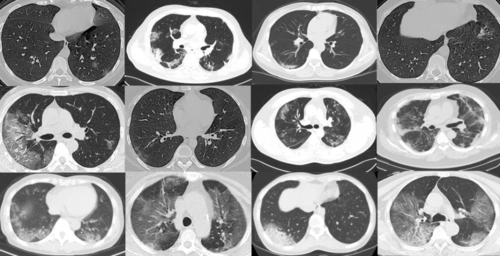

新冠肺炎呈阳性的 ct 扫描图像示例. 方法